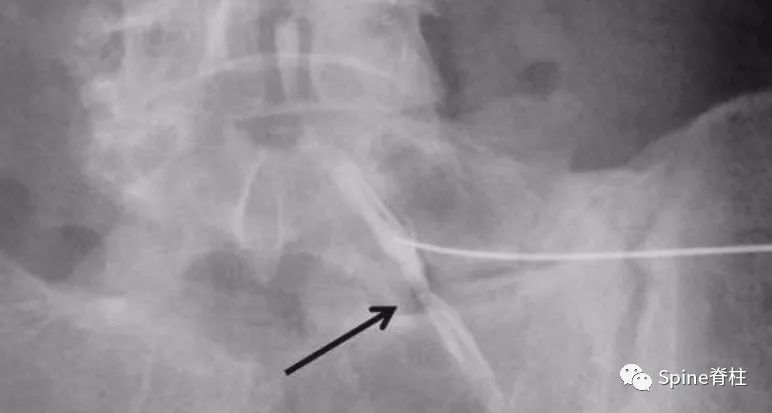

图: 远离综合征患者的MRI弥散张量成像显示的L5神经根在椎间孔外受卡压(箭头)

脊柱神经支配疼痛区域,脊柱神经支配的脏腑

图:远离综合征患者的MRI弥散张量成像显示的L5神经根在椎间孔外受卡压(箭头)